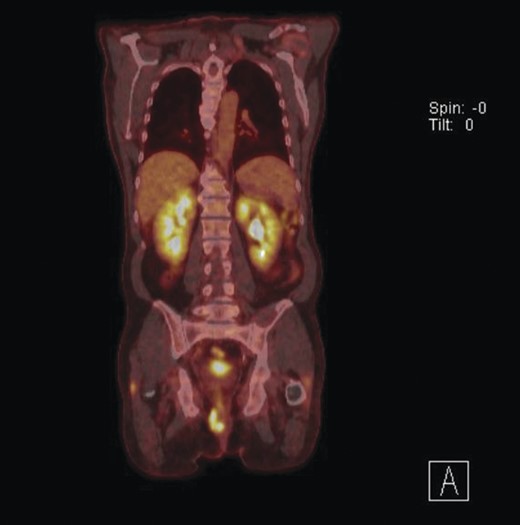

Given the high likelihood of significant vascular disease, a computed tomography (CT) angiogram was done (Fig. 1). Bilateral internal iliac artery stenosis was noted with complete occlusion of the inferior mesenteric artery and right internal iliac artery. A positron emission tomography (PET) scan showed only localized disease (Fig. 2). Magnetic resonance imaging (MRI) of his pelvis was significant for a large posterior abscess cavity with soft tissue at the margins with a cavity tracking superiorly along the posterior rectal plane (Fig. 3). The internal sphincter was noted to be necrotic on the last examination (Fig. 4) with a horseshoe cavity and a 10-cm tract running up the posterior aspect of the rectum. Multiple biopsies were taken from the anal margin, abscess cavity and peri-anal tissue, and the histology was consistent with diffuse large B-cell lymphoma. There were sheets of large atypical lymphocytes with extensive areas of necrosis. The tumour cells showed strong and diffuse immunohistochemical reactivity for CD20 (Fig. 5), indicating B-cell differentiation. The Ki67 proliferation index was very high (>90%) (Fig. 6) and there was positive in situ hybridisation (ISH) for Epstein-Barr virus (EBV) (Fig. 7). Fluorescence in situ hybridisation (FISH) was performed using a MYC dual colour break apart probe (8q24), and no rearrangement of the MYC gene region was detected. The combined morphological and FISH features were not considered to be those of Burkitt lymphoma.